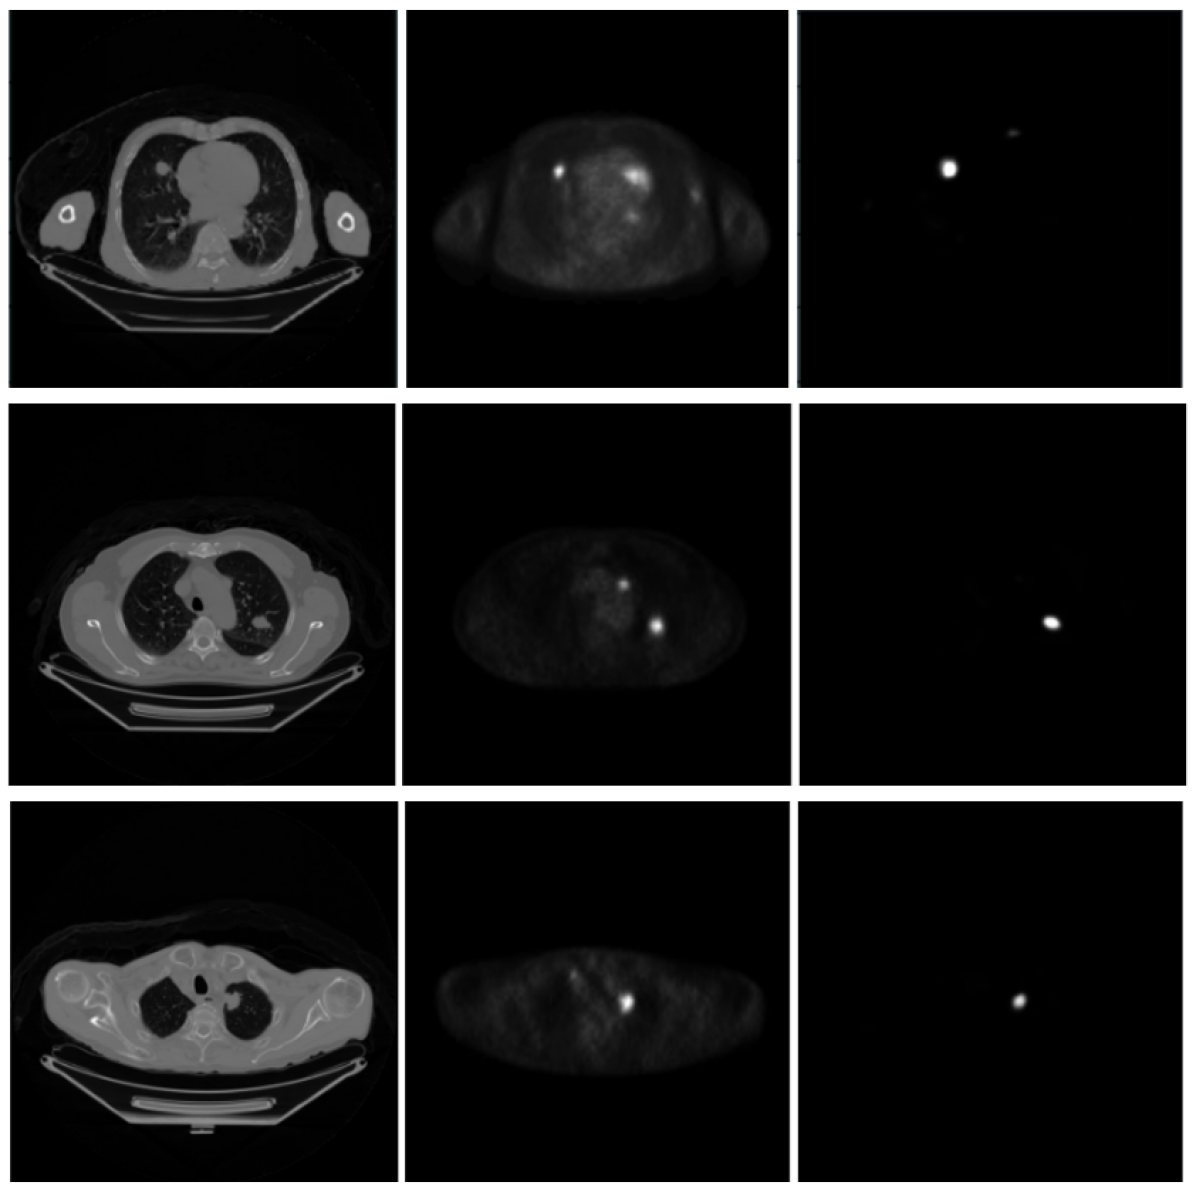

Refer to caption

Figure 5: Segmented results of lung nodules. The left image shows the original CT. The middle image is the ground truth. The right image shows the predicted lung nodule for lung cancer using our segmentation network..

The visualization of few representative examples of segmentation of nodules for lung cancer is presented in Fig 5. In addition, the proposed segmentation network shows highest performance in recognizing the lung nodules is confirmed with the reference PET image which is shown in Fig 8. The comparison of the performance of our proposed encoder with fully connected network outperforms the simple fully connected network and encoder and decoder followed by the fully connected layer.